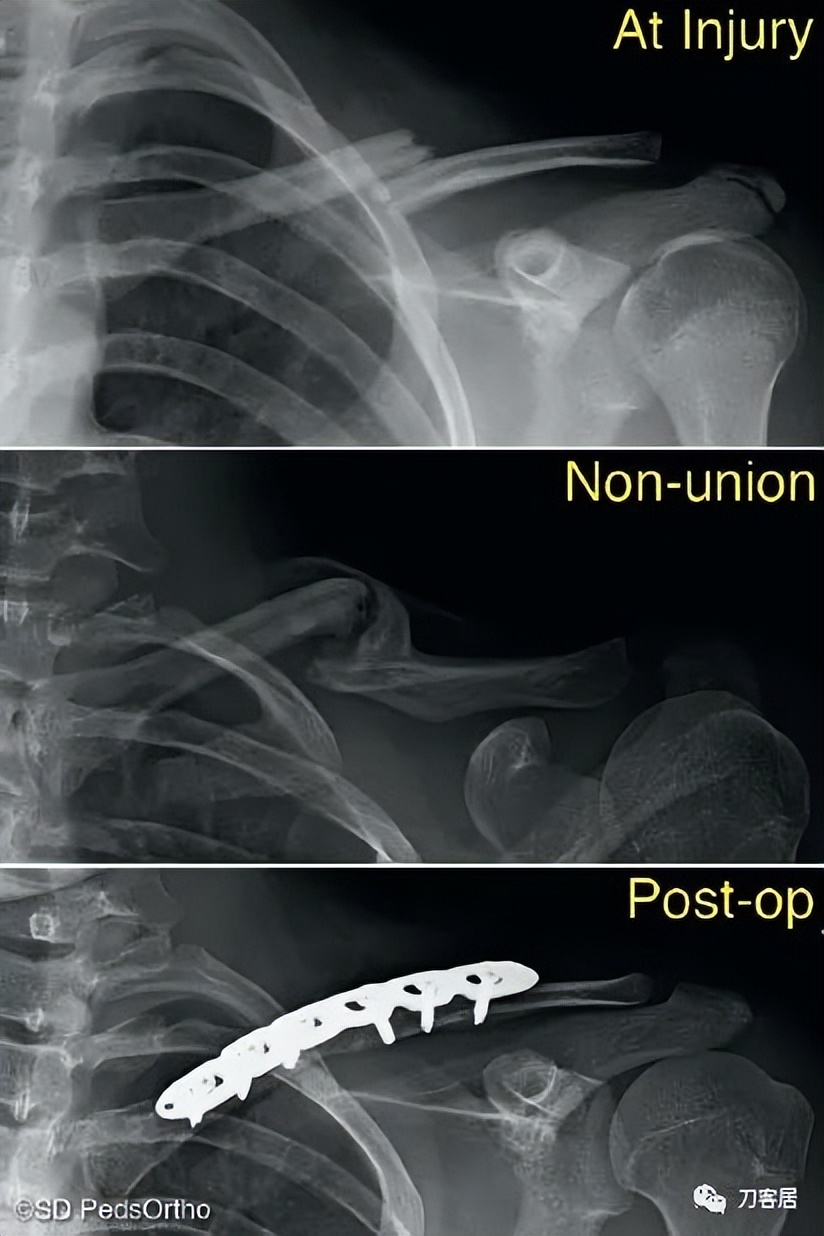

Figure 6-8 Although rare, clavicle nonunions can occur in children.

虽然罕见,但小儿锁骨骨折确实有骨不连发生的可能。

Although non-unions have been reported in as many as 15% of completely displaced clavicle fractures in the adult population, they remain an extremely rare complication in pediatric patients with less than a dozen cases having been reported in the literature (Fig. 6-8). Over the last 10 years, our institution has treated hundreds of midshaft clavicle fractures and we have only observed three non-unions all of which were successfully managed with local bone graft and plate fixation. We, therefore, do not believe that nonunion concerns in adolescent patients, even with displaced fracture patterns, justify acute surgery.

尽管成人完全移位的锁骨骨折存在15%的不愈合,但儿童患者完全移位的锁骨骨折不愈合极为罕见,文献报道的病例不到十几例(图6-8)。过去10年里,本单位治疗的数百例锁骨中段骨折,只有3例骨折不愈合,所有这些骨折不愈合均通过局部植骨和钢板固定成功治愈。因此,我们不认为青少年患者的锁骨骨折骨不连是个问题,即使骨折移位,也不能作为急性手术的理由。

For the rare midshaft clavicle fracture requiring surgery, plate fixation can be used for all fracture patterns. The rigid construct enables early mobilization and a rapid return to sports. Some centers are now using intramedullary stabilization with elastic nails for non-comminuted fracture patterns (Fig. 6-9); this minimizes the scar that results from open treatment. To date, no study has compared the results of plate fixation to intramedullary fixation in the pediatric population.

对于罕见的需要手术的锁骨中段骨折,钢板固定可用于所有骨折类型。刚性结构使早期活动和快速恢复运动成为可能。一些中心现在使用弹性钉进行髓内固定治疗非粉碎性骨折(图6-9);这可以最大限度地减少开放治疗造成的疤痕。迄今为止,尚无小儿锁骨严重移位骨折行钢板内固定和髓内固定的比较性研究。